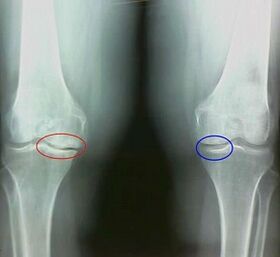

Например, каква е разликата между артрит и артроза на колянната става? С артрит се появява синовиалната обвивка на ставните тъкани. Това води до повишаване на температурата в ставата.

Ставата набъбва, се развива постоянен синдром на болката, засилвайки се по време на движение. С артрозата болката възниква само след физическа активност, можете да чуете характерна криза или кликвания в ставата, постепенно ставата се деформира и губи мобилност.

Както можете да видите, разликите в симптомите са незначителни: и в двата случая има болка, скованост и умора. Артритът и артрозата могат да повлияят на различни стави в човешкото тяло. С увреждане на гръбначния стълб и междупрешленните дискове се развива остеохондроза - тя е подобна на артрозата. В зависимост от мястото на заболяването, артрозата на глезена, рамото, тазобедрената става и така нататък се отличава.